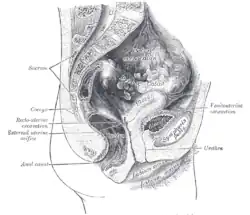

Secção sagital da parte inferior do tronco feminino, segmento direito

Secção sagital da parte inferior do tronco feminino, segmento direito -

Secção sagital mediana da pelve feminina.

Secção sagital mediana da pelve feminina.